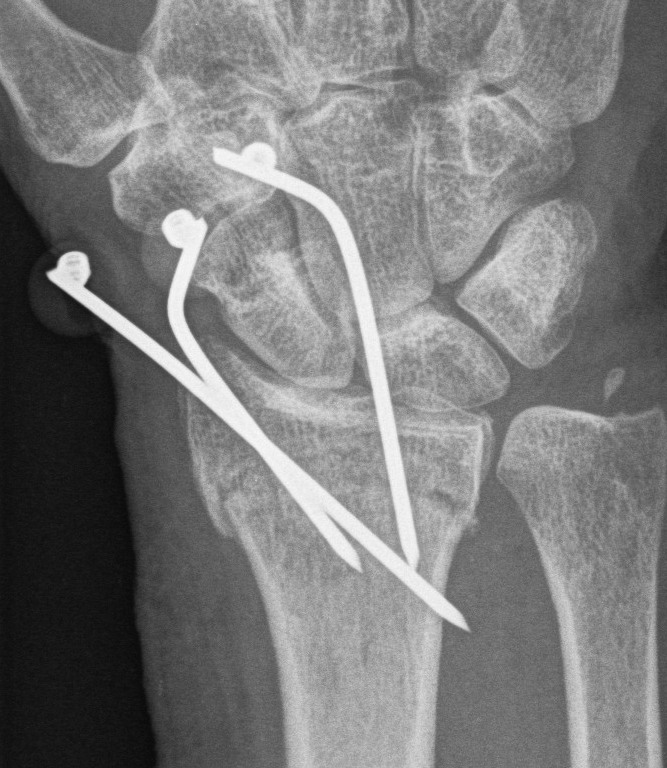

Distal Radius Fracture K wires APplateex fixbridge plate

K wires